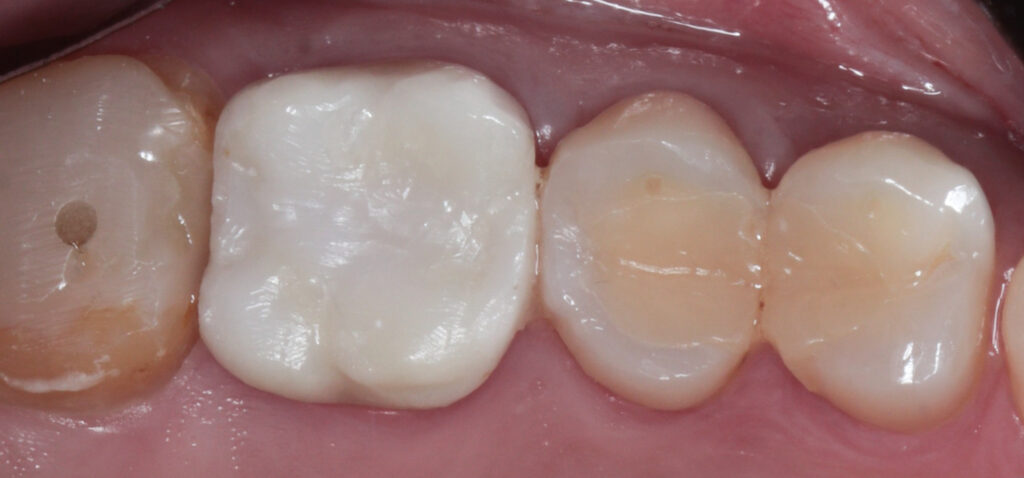

2. The Power of Temporization The “magic” happens during the healing phase. We placed high-quality provisional crowns for one month. This stage is crucial for:

3. The Final Restoration: Zirconium after one month, the soft tissue showed remarkable health and stability. We transitioned to the final Zirconium crowns with highly finished and polished not glazed cervical collar.